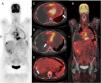

Paciente de 19 años con dolor centrotorácico y disnea progresiva reciente de grado II (NYHA). Inicialmente se constató cardiomegalia (fig. 1A), aumento de LDH y dímero D. Ante la sospecha de tromboembolia pulmonar, se realizó una tomografía computarizada (fig. 1B) que mostró una gran masa tumoral mediastínica con captación heterogénea de contraste y compresión de cavidades derechas. En una resonancia magnética con gadolinio (fig. 1C,D) se observó que la masa no tenía plano de separación con la aurícula derecha. Una mediastinoscopia diagnóstica posterior permitió el diagnóstico de angiosarcoma cardiaco. Para evaluar la extensión de la enfermedad, se solicitó una tomografía por emisión de positrones con 18F-FDG (fig. 2A: PET y B: PET-TC) que mostró hipermetabolismo cardiaco de predominio derecho con extensión pericárdica (fig. 2C), alguna adenopatía perilesional (fig. 2D) y 2 lesiones hipermetabólicas focales hepáticas (probables metástasis; fig. 2E), junto a derrame pleural derecho masivo. Estos hallazgos descartaron la posibilidad de rescate quirúrgico y se inició tratamiento sistémico con taxanos, doxorrubicina por lo que terapia de soporte. Pese a todo, la paciente falleció transcurridos 7 meses a consecuencia de fallo cardiaco compresivo.